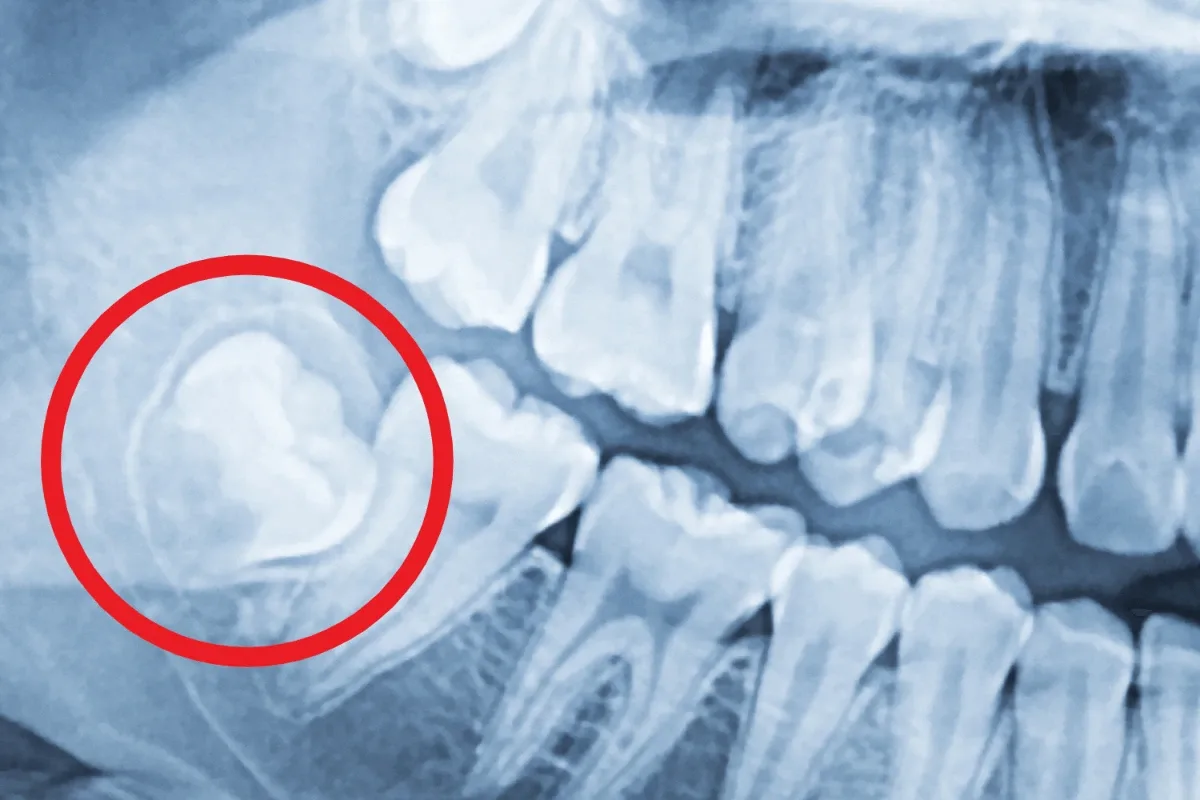

Digital X-Rays for Precision

We use digital imaging to assess the exact position of your wisdom teeth and plan the safest, most efficient extraction approach.

Before the procedure, we take digital X-rays to assess the position of your wisdom teeth and how many you have (most people have between one and four). You'll be placed under anesthesia nitrous oxide or IV sedation, depending on your case for your comfort throughout the procedure.